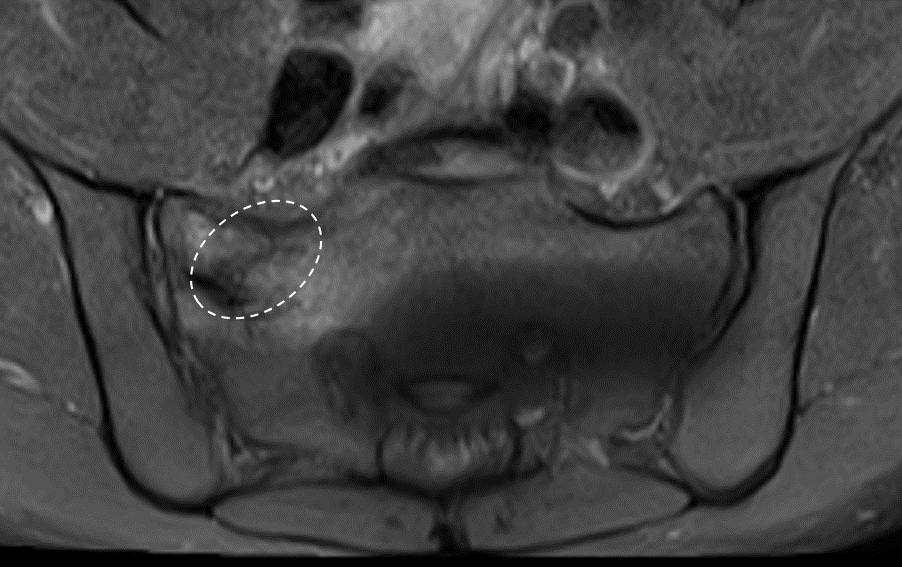

- MRI (Magnetic Resonance Imaging): Often used to evaluate soft tissue inflammation, fluid buildup, or subtle bone changes that may not appear on X-rays.

When the patient resumed running just two months after the fusion surgery, the stress that the SI joint would typically absorb was instead redirected to the symphysis pubis. This excessive strain led to the rapid onset of severe osteitis pubis. Imaging studies (X-ray and CT scan) revealed significant damage: the normal space within the symphysis pubis, which houses the fibrous disc, had disappeared entirely, and the surrounding bone exhibited marked erosion.

The images below, taken several months after the orthobiologic procedure, demonstrate significant improvement in the condition of the symphysis pubis joint.

The follow-up images indicate a restored joint space in the symphysis pubis, with improvements in the surrounding bone structure. The patient reported noticeable improvement, noting that 80–90% of his symptoms had diminished and that he experiences minimal daily discomfort. This outcome illustrates the potential role of orthobiologic procedures in supporting joint health and function.